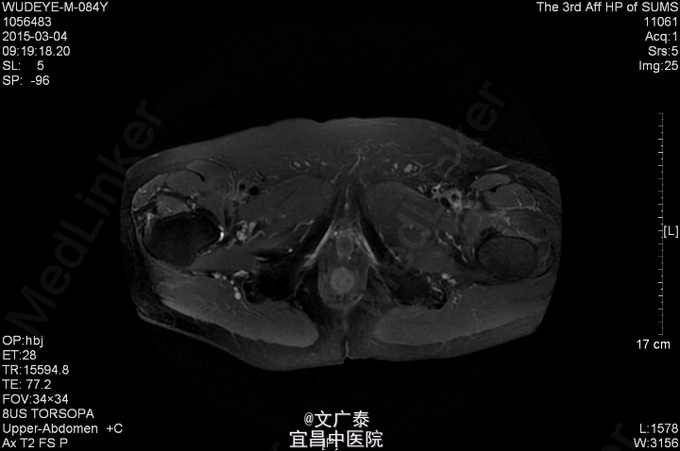

1、TURP加双侧睾丸切除术后11年 2、患者于11年前在本院行前列腺电切术加双侧睾丸切除术后,术后病理回报:前列腺腺癌,(Gleason评分:4+5=9分)。术后予以康士得(50mg qd )内分泌治疗2年后改用福至尔(250mg tid)治疗至今。复查tPSA: 2011.02 tPSA:1.00 ng/L,2012.02 tPSA:0.804 ng/L,2013.02 tPSA:1.23 ng/L,2014.11 tPSA:2.57 ng/L。

3、直肠指检:肛门括约肌正常,前列腺不大,无触痛,表面光滑,质韧,边缘清楚,中央沟存在,未触及明显结节,指套未见染血。余无异常 4、盆腔MR:前列腺癌术后。核素PET/CT全身:1.前列腺癌术后,局部软组织灶,未见明显异常代谢,考虑疤痕形成可能性大;

5、前列腺电切术后 双侧睾丸切除术后 6、拟行粒子植入手术,术后患者未诉明显不适,术后恢复可,PSA降至正常